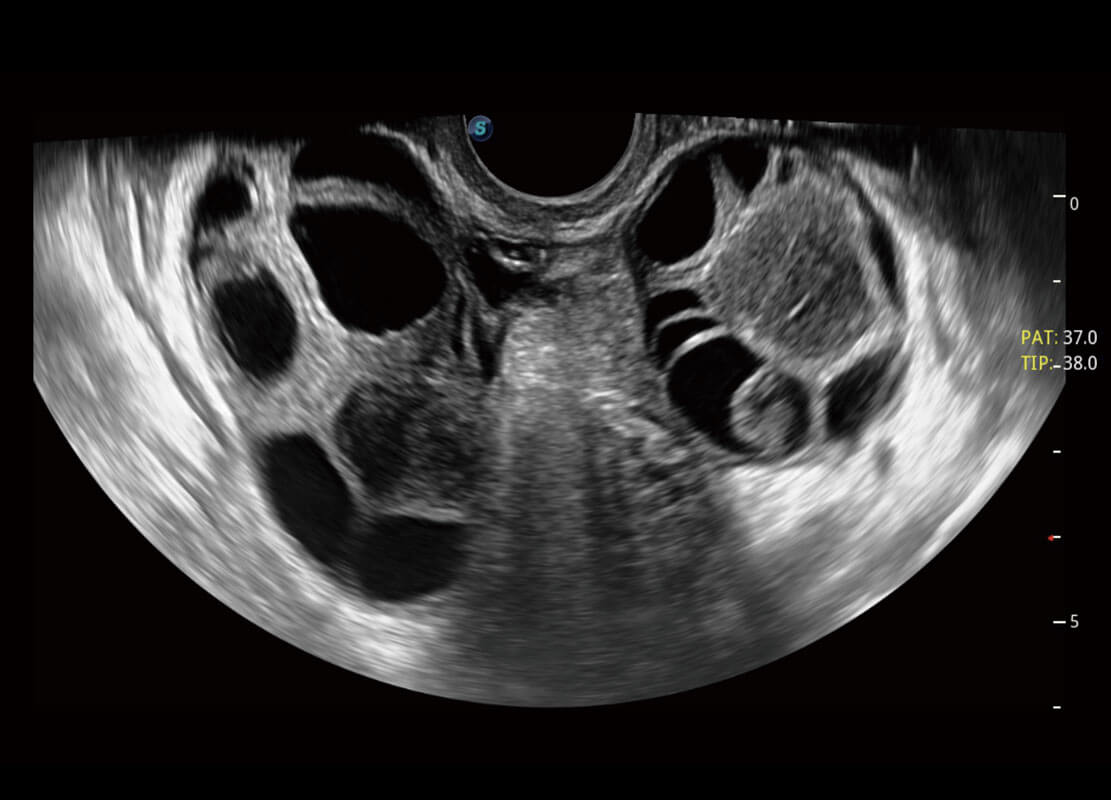

P60为盆底超声检查提供应用方案,多种腔内及腹部容积探头提供从二维、三维到四维的优异图像品质,实时快速三维容积数据获取,专业的测量工具包等人性化设计,为超声医生诊断提供有力保障。

Lev.Hiat A-r: 16.33 cm2

Lev.Hiat H-r: 53.70 mm

Lev.Hiat W-r: 43.96 mm

Lt-LUG-r: 24.16 mm

Rt-LUG-r: 19.94 mm

能够简化盆底检查的操作流程,可在二维模式及三维成像模式下实现一键自动提取出标准切面、自动识别当前切面、自动测量,提升盆底检查的高效性,同时也能让青年医生快捷的获得准确的检查结果。